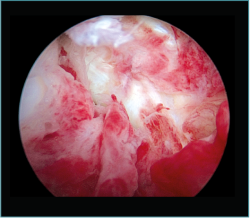

Método: hemos revisado 38 pacientes con codo rígido postraumático o degenerativo que se trataron mediante artrolisis artroscópica entre 2013 y 2016, con un seguimiento medio de 25 meses (38-15). Según la etiología de la rigidez, clasificamos a los pacientes en 2 grupos: grupo 1, los pacientes con rigidez por patología degenerativa del codo, y grupo 2, los pacientes con rigidez postraumática. Clasificamos la rigidez siguiendo la escala de Morrey y utilizamos la escala funcional Mayo Elbow Performance Index (MEPI), que evalúa el dolor, la movilidad, la estabilidad y la función del codo pre- y postoperatoriamente. Describimos los procedimientos artroscópicos realizados en cada paciente, que incluyen la sinovectomía, el desbridamiento de tejido fibroso, la capsulectomía anterior y/o posterior, la resección de osteofitos en la parte anterior y posterior del codo, la extirpación de cuerpos libres y la liberación “abierta” del nervio cubital.

Method: a review was performed on 38 patients with stiff elbow due to degenerative or post-traumatic reasons, and who were treated by arthroscopic arthrolysis between 2013 and 2016, with a mean follow-up of 25 months (38-15). Elbow stiffness was classified following the Morrey scale and the Mayo Elbow Performance Index (MEPI) functional scale was used to evaluate pain, mobility, stability and elbow function pre- and post-operatively. The arthroscopic procedures performed on each patient are described, including synovectomy, debridement of fibrous tissue, anterior and/or posterior capsulotomy, resection of osteophytes in the anterior and posterior part of the elbow, extirpation of loose bodies and open release of the ulnar nerve.